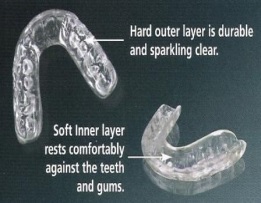

Your dentist can fit you with a mouth guard to protect your teeth from grinding during sleep.